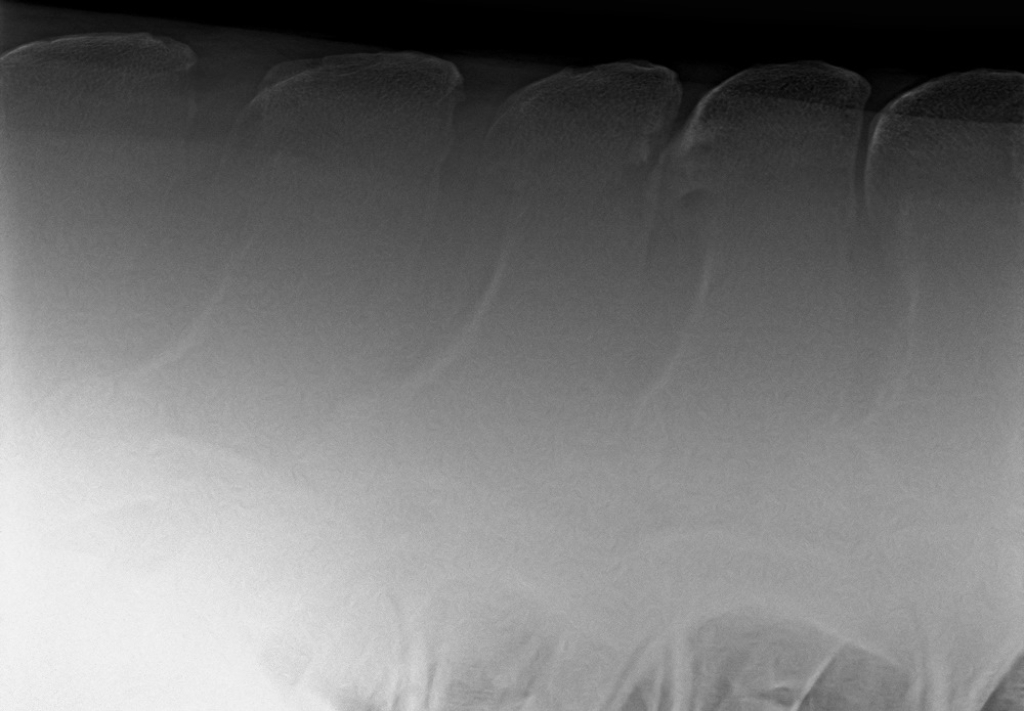

Foto: Röntgenfoto van een ernstige vorm van kissing spines en spondylose (versmelting van de wervels)

Kissing spines is een beladen term en een gevreesde aandoeningen bij paarden. Bij kissing spines komen de doornuitsteeksels van de ruggenwervels dichter bij elkaar te staan of komen zelfs tegen elkaar aan. Dit kan leiden tot irritatie van het bot van de doornuitsteeksels en daardoor veranderingen van de vorm van de doornuitsteeksels en het bot van de spinaaluitsteeksels zelf. Ook spelen veranderingen bij de aanhechtingen van de spinaalligamenten een rol in dit probleem. Niet alle veranderingen van de doornuitsteeksels zijn echter pijnlijk of een reden voor (rug)klachten. Belangrijk is om verschil te maken tussen de röntgenologische diagnose kissing spines en de klinische diagnose (oorzaak van pijn of probleem). Daarom is de diagnose van kissing spines niet altijd even eenvoudig te stellen. Meestal is een uitgebreid klinisch onderzoek aangevuld met beeldvorming van de wervelkolom noodzakelijk om een correct diagnose te stellen en andere oorzaken uit te sluiten.

Of er sprake is van Kissing spines is meestal eenvoudig vast te stellen op röntgenopnames van de rug. Of die röntgenologische veranderingen ook echte de oorzaak zijn van de klachten is echter lastiger om aan te tonen. Er is namelijk niet altijd een duidelijk verband tussen de klachten en (röntgenologische) veranderingen van de doornuitsteeksels. Dat er dus kissing spines op een röntgenfoto worden ontdekt betekent niet automatisch dat het paard daar last van heeft. Wel is er aangetoond dat des te meer en heftiger de veranderingen zijn, des te groter de kans is dat ze aanleiding geven tot rugpijn. Ook is er aangetoond dat rugpijn bij paarden met kissing spines vaker voorkomt in combinatie met andere problemen zoals een (milde) kreupelheid, artrose van het SI gewricht of artrose van de facetgewrichten.